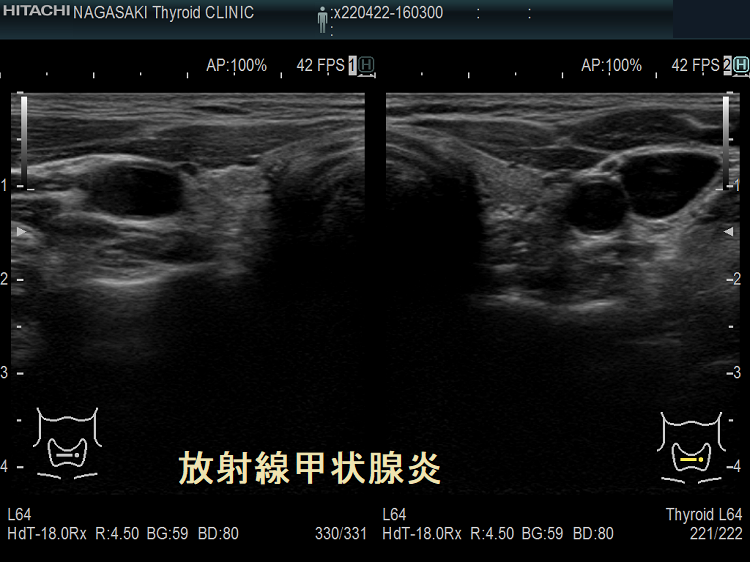

放射線甲状腺炎は、甲状腺以外の癌(頭頚部癌、頭頚部の悪性リンパ腫、頭頚部が照射野に入る肺癌・食道癌・乳癌など)に対する放射線外照射(体の外から放射線を当てる事)が原因で起こります。

放射線量により発症までの期間は異なり、数か月〜数十年後とされます。外部からの放射線量が26 Gyを超えて甲状腺組織の破壊が強いと、甲状腺は萎縮し甲状腺機能低下症に至ります。

子宮頸がん頸部リンパ節転移に放射線外照射した後の放射線甲状腺炎 超音波(エコー)画像 超音波(エコー)画像 (拡大);内部は等エコー、比較的均一。